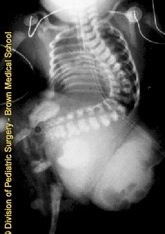

Severe scoliosis can cause a variety of health problems ranging from musculoskeletal to cardiopulmonary dysfunction. A severe scoliosis of the thoracic spine can lead to diminished lung volume (or hypoplastic lung if the curve obstructs the thoracic cavity during lung growth) and can sometimes cause heart problems due to the spine putting direct pressure on the heart.

This child’s scoliosis is clearly obstructing his/her right chest cavity. Lung development and volume will be mechanically inhibited.